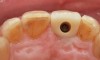

Fig 6. Incisal view (clinical) of implant-retained crown demonstrating ideal position of access opening in the cingulum using the angulated screw channel.

Figure 6